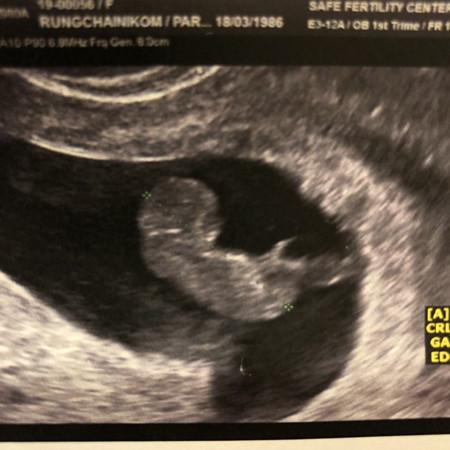

10w5d วันนี้อัลตราซาวครั้งที่4 3ครั้งแรก ได้ยินเสียงหัวใจตามลำดับ หมอชมน้องแข็งแรงดีมาก วันนี้ซาวครั้งที่4 หัวใจน้องไม่เต้นแล้ว ช็อค อึน มึน เสียใจ.. น้องเกิดจาก อิ๊กซี่เด็กหลอดแก้วค่ะ ตอนนี้บรรยายความรู้สึกไม่ออกจริงๆ และน้องก็ยังอยู่ในท้อง นัดวันดูดออกแล้วค่ะ น้องมาลาแม่ๆทุกคนนะคะ ขอให้หนูไปสู่ภพภูมิที่ดีนะลูก แม่จะรอหนู ให้หนูมาอยู่กับแม่ใหม่นะ ❤️ แชร์ประสบการณค่ะ TT